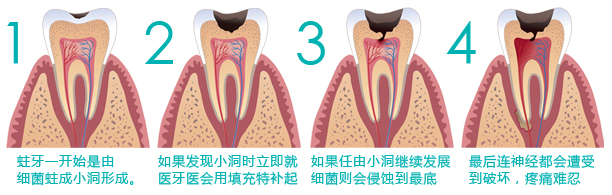

龋齿是指什么

龋齿俗称蛀牙,世界卫生组织将龋齿列为重点防止的三大非传染性疾病之一。俗话说“牙疼不是病,疼起来要命”,牙疼就是这么折磨人。平时不注意口腔清洁,使得牙齿表面的细菌分解食物中的糖分,产生酸性物质,腐蚀牙齿,从而导致龋齿。

蛀的那部分会变黑,慢慢发展,龋齿的腐蚀程度越来越大,逐渐半颗牙齿就没有了。龋洞不经过治疗是不会自行愈合的,继续发展会持续引发牙髓炎和根尖周炎,较 终结果是牙齿丧失。严重时甚至能引起牙槽骨和颌骨炎症。